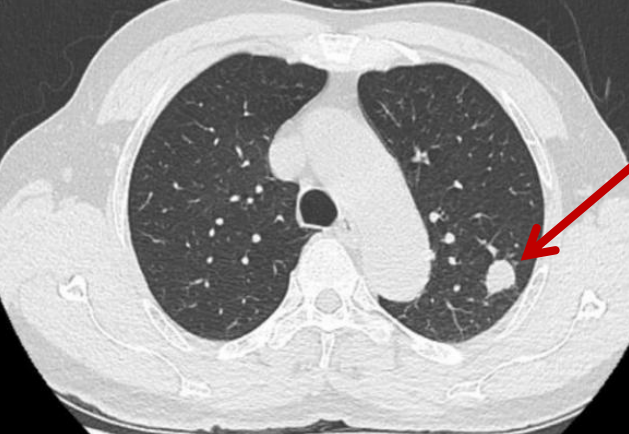

67 岁的吴先生(化名)则有着更复杂的病史:2012 年,他曾因为下肢恶性黑色素瘤,在外院做了左小腿中下段截肢手术。入院前 2 周,他在当地医院检查时,发现左肺上叶长了个「结节」,穿刺活检后明确诊断——恶性黑色素瘤肺转移。

胸心血管外科团队详细了解吴先生病史,认真研究胸部 CT:「幸好是单个转移瘤,且处于『优势』位置,可行胸腔镜手术切除治疗,改善预后。」吴先生也希望少点传统手术的 「大折腾」:「能少插根管子就少遭点罪,还能快点恢复。」